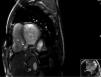

Although the patch significantly reduced the interventricular communication, a residual defect remained, with turbulent left-to-right shunt, draining into a cavity that corresponded to the aneurysmal dissection of the septum, and that communicated distally with the right ventricle (Figure 2), findings confirmed by cardiac magnetic resonance imaging (Figures 3 and 4).

Cardiac magnetic resonance image from cine balanced steady-state free procession sequences (bright blood), short-axis view at the level of the basal ventricular segments. There is a residual defect in the posterior interventricular septum, communicating with a neocavity formed by the aneurysmal dissection of the septum. LV: left ventricle; NC: neocavity formed by the dissection of the interventricular septum; RV: right ventricle. Arrow: interventricular septal rupture; asterisk: residual ventricular septal defect.

Cardiac magnetic resonance gadolinium perfusion imaging. Immediately after contrast injection, flow can be seen from the left ventricle into the cavity formed by the interventricular septal dissection, which finally drains into the apical region of the right ventricle. LV: left ventricle; NC: neocavity formed by the dissection of the interventricular septum; RV: right ventricle. Asterisk: residual ventricular septal defect.